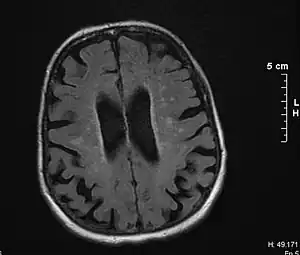

Binswanger's disease can usually be diagnosed with a CT scan, magnetic resonance imaging, and proton magnetic resonance spectrography in addition to clinical examination. Indications include infarctions, lesions, or loss of intensity of central white matter and enlargement of ventricles, and leukoaraiosis. A Mini–Mental State Examination has been created to quickly assess cognitive impairment and serves as a screening test for dementia across different cultures.[13]

Leukoaraiosis refers to the imaging finding of white matter changes that are common in Binswanger disease. However, leukoaraiosis can be found in many different diseases and even in normal patients, especially in people older than 65 years of age.[5]

There is controversy whether leukoaraiosis and mental deterioration actually have a cause and effect relationship. Research has shown that different types of leukoaraiosis can affect the brain differently, and that proton magnetic resonance spectroscopy would be able to distinguish the different types more effectively and better diagnose and treat the issue.[9] Because of this information, white matter changes indicated by magnetic resonance imaging or computerized tomography cannot alone diagnose Binswanger disease, but can aid to a bigger picture in the diagnostic process. There are many diseases similar to Binswanger's disease including CADASIL syndrome and Alzheimer's disease, which makes this specific type of white matter damage hard to diagnose.[5] Binswanger disease may be diagnosed by a team of experts including a neurologist and psychiatrist to rule out other psychological or neurological problems.[3] Because doctors must successfully detect enough white matter alterations to accompany dementia as well as an appropriate level of dementia, two separate technological systems are needed in the diagnosing process.

Much of the major research today is done on finding better and more efficient ways to diagnose this disease. Many researchers have divided the magnetic resonance imaging of the brain into different sections or quadrants. A score is given to each section depending on how severe the white matter atrophy or leukoaraiosis is. Research has shown that the higher these scores, the more of a decrease in processing speed, executive functions, and motor learning tasks.[14][15] Other researchers have begun using computers to calculate the percentage of white matter atrophy by counting the hyper-intense pixels of the magnetic resonance images. These and similar reports show a correlation between the amount of white matter alterations and the decline of psychomotor functions, reduced performance on attention and executive control.[16][17] One type of technology is called susceptibility weighted imaging (SWI) which is a magnetic resonance technique which has an unusually high degree of sensitivity and can better detect white matter alterations.[18]